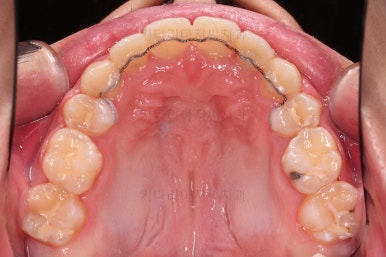

초진 시, 입안의 모습입니다.

치아를 모두 담기에 골격이 매우 작았어요.

이런 경우 치열이 ㅃ뚤어지거나 입이 튀어나오거나 뻐드렁니가 되거나 특정 치아가 묻혀버리거나 맨 뒤치아가 마치 사랑니처럼 올라오지 못한다거나 등등의 문제가 생기는데요.

이번 환자분은 전반적으로 삐뚠 상황이었어요.

앞니도 대칭적으로 삐뚤어져 흔히 나비치아라고 하는 형태로 보이고, 아랫니들은 U자 아치의 형태가 찌그러져 있네요.

당연히 교합도 맞지 않고요.